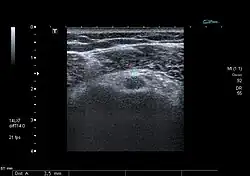

Intakte Bizepssehne (schwarz), welche im Bereich des Sulcus bicipitalis vom Ligamentum transversum humeri (A) überbrückt wird.